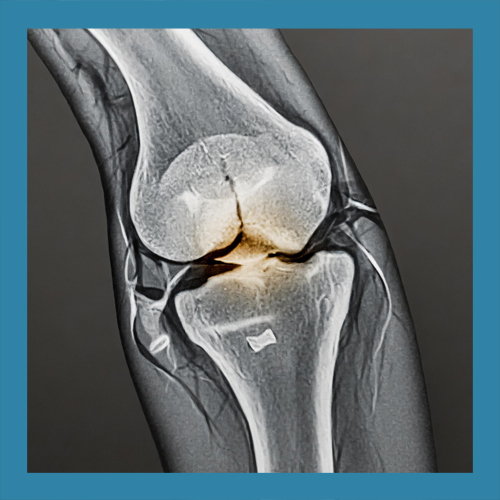

• 반월상 연골이란 무엇일까요?

반월상 연골은 무릎 관절 내에 위치한 반달 모양의 연골 조직으로, 관절 사이의 충격을 흡수하고 관절의 안정성을 유지하는 역할을 합니다. 좌우로 각각 하나씩 존재하며, 무릎이 움직일 때 발생하는 마찰을 줄이고 관절 연골의 손상을 예방합니다. 이 조직은 혈액 공급이 제한적이기 때문에 손상 시 자연 치유가 어려운 경우가 많습니다.

반월상 연골 파열의 치료는 손상의 위치와 정도에 따라 다르게 접근해야 합니다. 경미한 파열은 보존적 치료로 충분히 회복될 수 있지만, 심각한 경우에는 수술이 필요할 수 있습니다. 이를 정확히 판단하기 위해 MRI와 같은 정밀 검사가 필수적입니다.